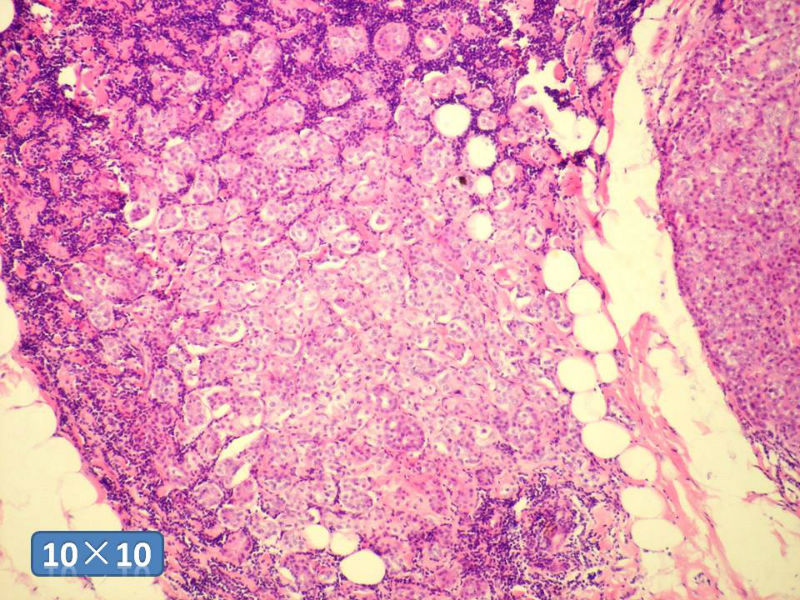

女性,50岁,乳腺肿物,冰冻切片(图1-25)